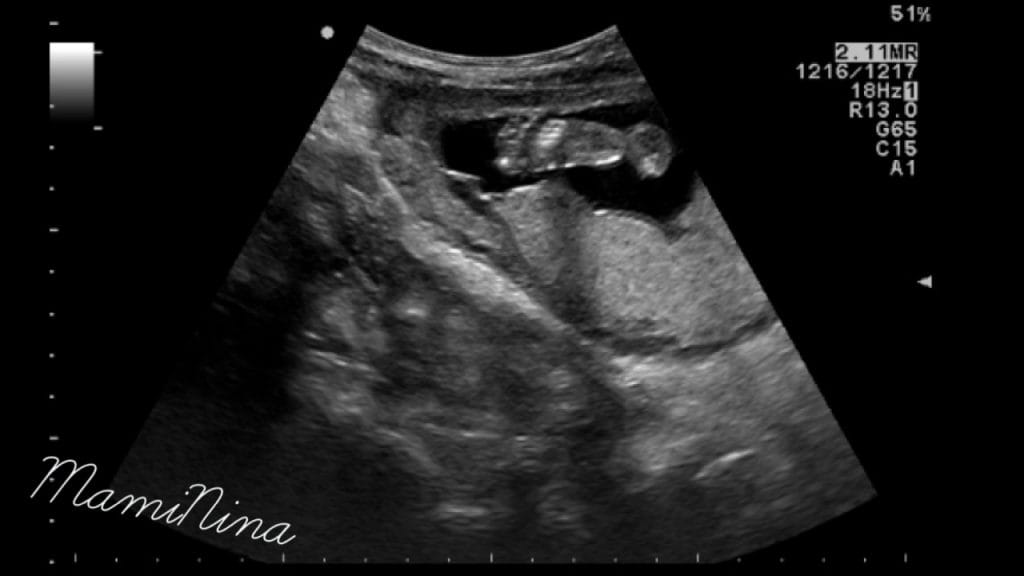

Zdravnica je izmerila dolžino maternice in pričela z ultrazvočnim pregledom. Za začetek z odličnim pogledom na utripajoči srček in njegove štiri prekate. Skozi pregled smo pregledali prav vse od začetka do konca, rokice, nogice, hrbtenico, rebra, usta, oči, res, ni da ni. Izredno se je potrudila in nama z možem pokazala vse, kar je le lahko. Pogledali smo tudi, kako je plod ravno v trenutku, ko smo opazovali profil obrazka nekaj prav na veliko pogoltnil, kar je bilo res prav zanimivo.

Med pregledom je bil seveda, tako kot vsak dan, v trebuščku pravi nogometni trening, zato smo tudi na ekranu videli, kako se premikajo roke in noge in kako je proti koncu pregleda začel plod svojo zadnjico tiščati ob trebušno steno. Vse skupaj res odlično čutim, saj se posteljica tokrat nahaja za gestacijsko vrečko, pri prvi sem vse skupaj čutila precej kasneje, ker je bila posteljica pred vrečko. Vodilni plodov del je zaenkrat glava in kar precej upam, da pri tem tudi ostane. Zaradi prvega poroda, ki se je končal s carskim rezom ravno zaradi medenične vstave, je tokrat, v primeru, da bo otrok spet sedel na ritki, skoraj sigurno edini možni porod zopet carski rez. Vseeno upam, da bom tokrat lahko dobila drugačno izkušnjo, katere me je, ne glede na izid, počasi že rahlo strah (priznam).

(na dodanih slikah lahko vidite glavico, nogico in profil obrazka naše princeske)